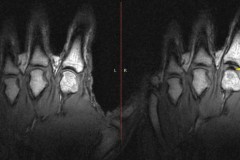

Giống như sụn tự nhiên, sụn nhân tạo cũng chống lại căng cứng và phục hồi hư tổn bằng cách hấp thụ nước. Ảnh dẫn theo Innovation Toronto